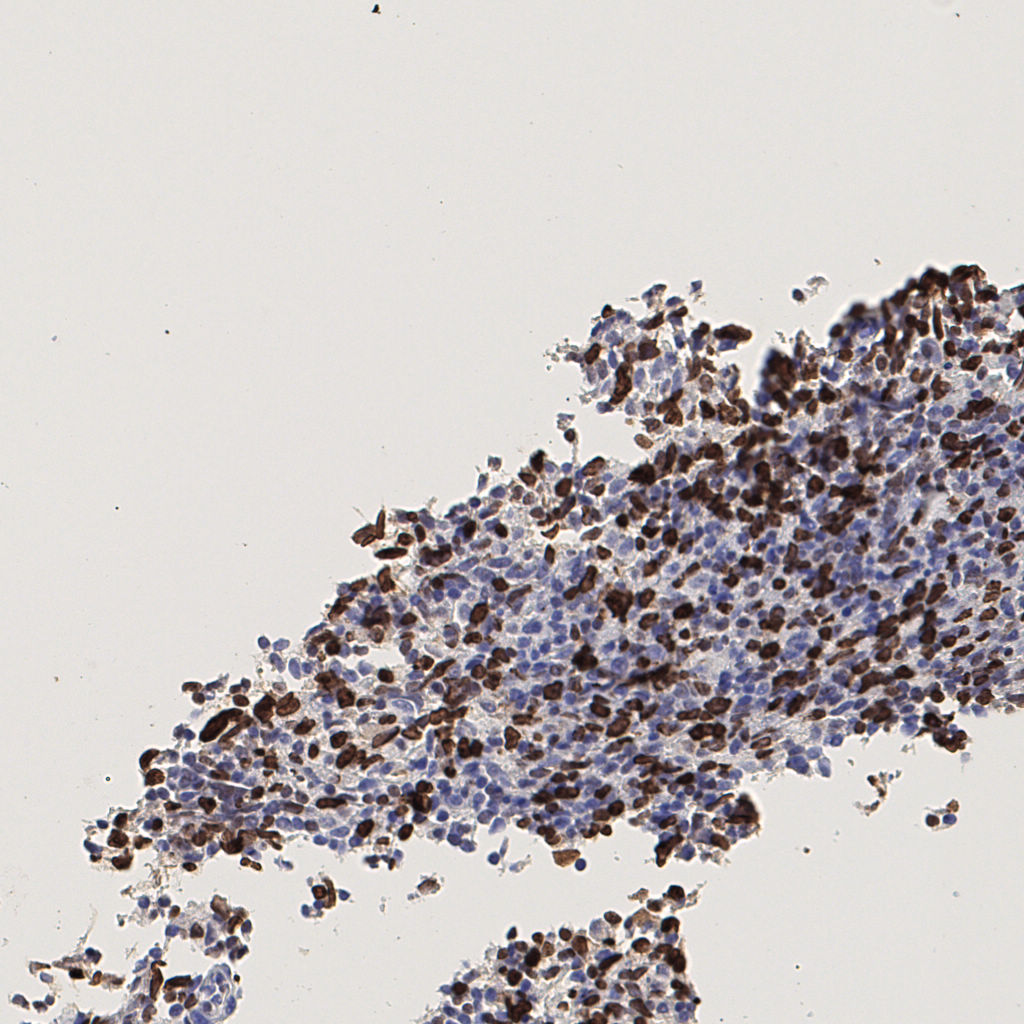

7.85%

Ki67 指数

阴 1104 阳 94

切片统计

总切片 1953

有效 288

已标记 288

有效率 15%